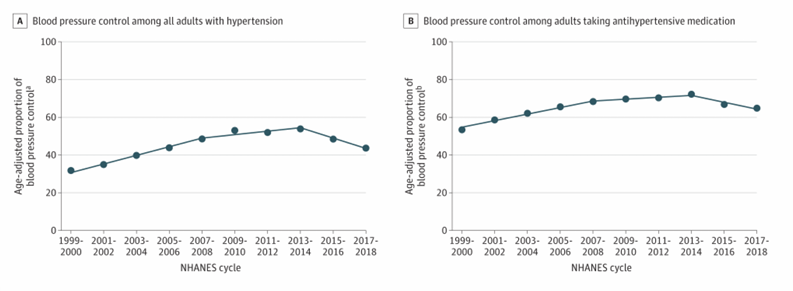

summary